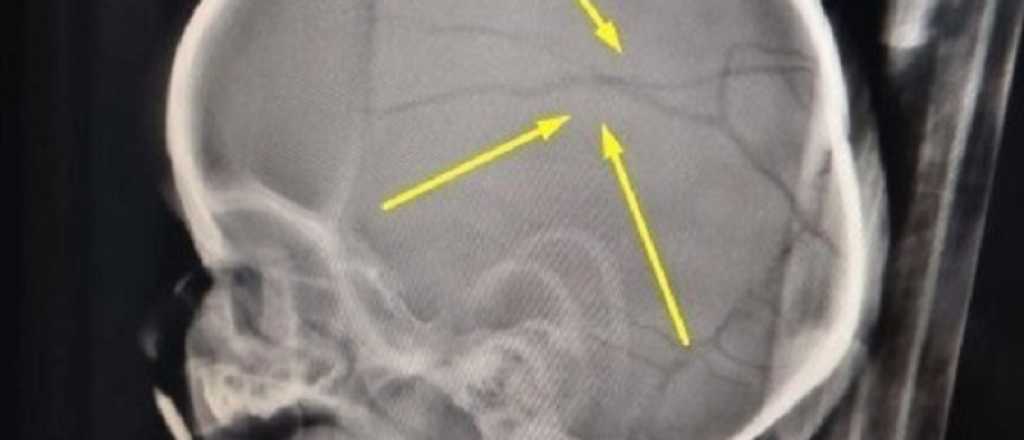

Roth había sido condenado a tres años y un mes de prisión por "lesiones graves y leves" contra una nena de 2 años, hija de una ex pareja, a quien envió al hospital con fractura de cráneo y lesiones compatibles con mordeduras. Sin embargo, gracias a un fallo del juez de Ejecución Penal N° 2 de Bahía Blanca, Onildo "Yiyo" Stemphelet, el agresor consiguió la libertad asistida en base a un informe del Servicio Penitenciario Bonaerense que lo calificaba con conducta "ejemplar 10" y concepto "bueno".

Según la investigación, Roth mantuvo encerrada durante tres días a su pareja de 19 años, a quien golpeaba y controlaba constantemente. La joven sólo podía salir al patio y debía entregar su celular para ser revisado. El episodio más grave recayó sobre el hijo de la mujer, un bebé de 11 meses, que sufrió múltiples fracturas en el cráneo producto de los golpes.

El niño fue trasladado de urgencia al Hospital Penna de Bahía Blanca, donde este jueves permanecía internado en terapia intermedia, fuera de peligro. La joven también presentaba hematomas en el rostro, cuello y brazos.